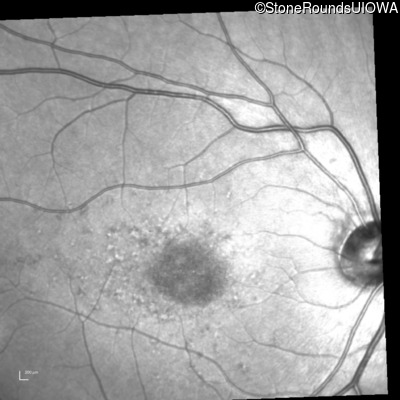

Infrared Fundus Photograph - Right - 20/80 -1

Exemplar

Infrared Fundus Photograph - Left - 20/80